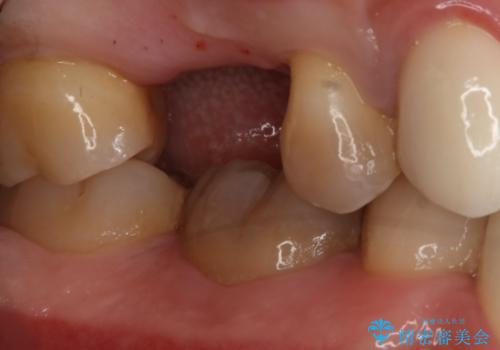

- 右上6番の歯の欠損部の治療を希望され来院された患者様です。

インプラント治療を希望されたので、インプラントとセラミッククラウンでの治療を計画しました。

歯の欠損部への治療には入れ歯・ブリッジ・インプラントという治療が選択されますが、インプラント治療は天然歯を削ることなく治療を行うことが出来ます。